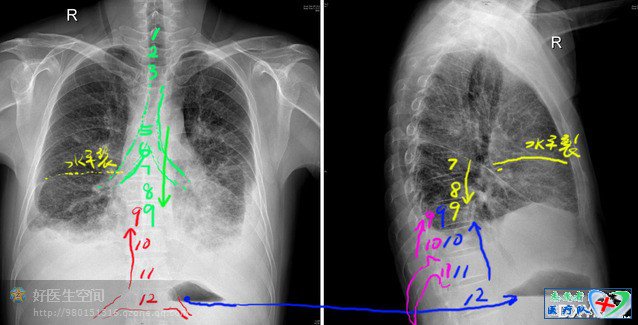

现在进入实战阶段,我用5中方法(不同的颜色)数骨头,为胸水定位

1、先用胸锁关节定位标出1,2,3 胸椎,这个片子照的不是很正,下面数不清楚,

不要紧,抓住气管分叉,标出6、7、8、9 关键的9出来了,这个刚好对着膈肌顶端被胸水淹没,左右两侧胸水凸起最高处应该在9胸椎中上缘

2,从第12胸椎往上数很容易定出9胸椎(当然不是每回都有这么好的运气

3,用水平裂往下数7、8、9

4侧位上最长最下的肋骨不会是12肋因为12肋很小经常在侧位被遮住,可以肯定这个是11,往上数11、10、9

5,有个胃泡水平,可以用的上,左右对照,确定12胸椎,往上数,有点像心电图12导同步找P波的方法

所以这个人胸水是少量上限,快到中量了